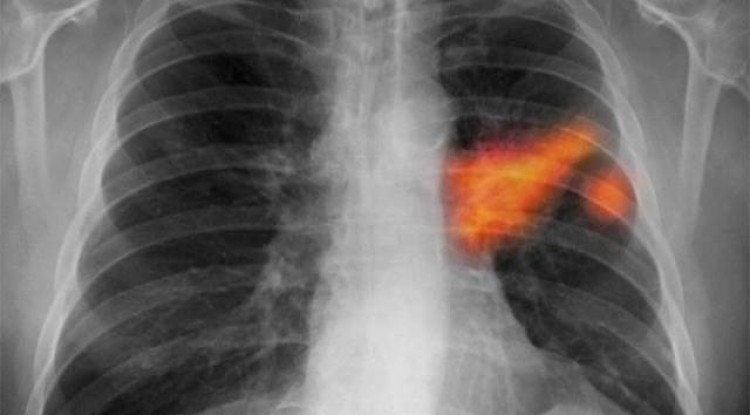

La primera inmunoterapia selectiva para el cáncer de pulmón está disponible en el país